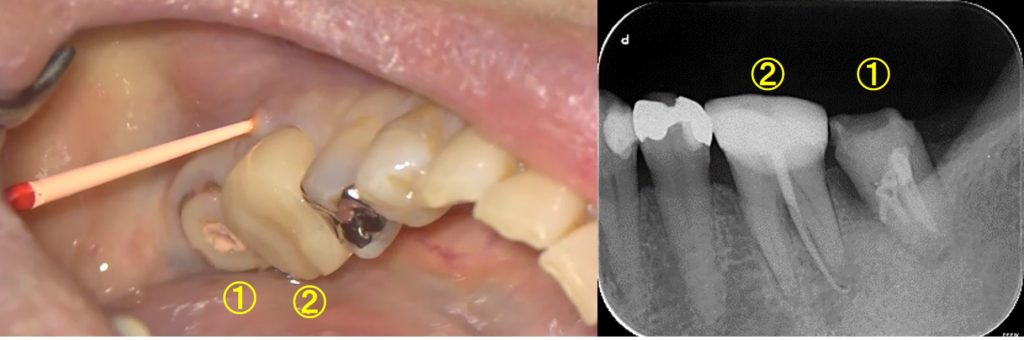

同時に後方の歯の根管治療をおこなうと、クラウン装着した歯ぐきが腫れて痛むようになりました。患者様は、「根管治療した歯①が痛む?」と思い、当院を受診されましたが、原因は、クラウンを被せた歯②にありました。

本動画は、②の歯の根管治療の様子です。

レントゲンでみると問題がないように見えましたが、腫れの原因は②の歯根の先端にあることが分かります。